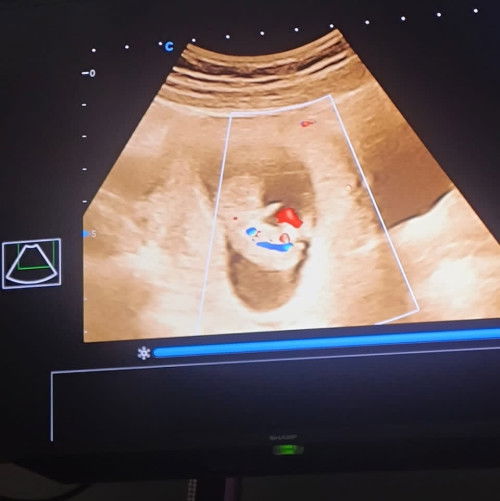

Usg kehamilan 10w HPL MARET

Baru banget usg pertama kali nih bun diusia 10minggu dan alhamdulillah semua normal tangan dan kaki udah keliatan djj udah kedengeran dan aktif banget ada yang sama gak bun sharing” yuk trs nnti usg ke 2 pas berapa minggu yha bun? #sharing #bantujawab #firstmom